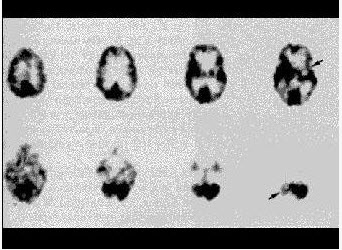

41、多项选择题

男性,8岁,既往有多次抽搐病史,行99Tcm-ECD脑显像(图1),6天后复查(图2),诊断是()。

A.左侧颞叶局限性癫痫病灶

B.图A为发作期

C.图B为发作期

D.左侧顶叶癫痫病灶

E.左侧额叶癫痫病灶